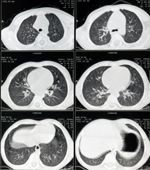

The new ALA guidelines state that individuals who are current or former smokers, aged 55 to 74 years, with a smoking history of at least 30 pack-years (one pack per day for 30 years), and with no history of lung cancer should be screened. The group emphasized that only CT scans should be used, and not chest x-rays.

Lung cancer screening remains controversial, even after the results of the National Lung Screening Trial (NLST) were published last summer. That study included 53,454 high-risk individuals and compared CT scans to chest x-rays. CT scanning lowered mortality due to lung cancer, as well as from any cause, by 20.0% compared with radiography. There were, however, high rates of false positives in both the CT group (96.4%) and the radiography group (94.5%).